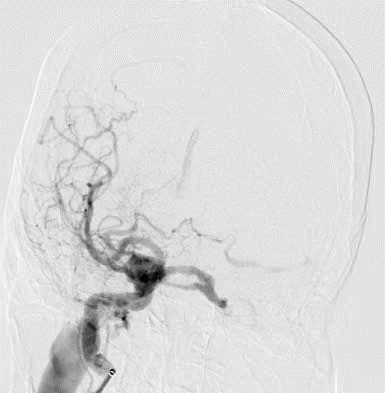

Bệnh nhân N được chỉ định can thiệp nội mạch – phương pháp điều trị phổ biến và hiệu quả nhất hiện nay. Thủ thuật sử dụng vòng xoắn kim loại (coil) để bít tắc đường dò bất thường, khôi phục lưu thông máu bình thường trong hệ tuần hoàn não. Sau phẫu thuật 1 ngày, tình trạng bệnh nhân cải thiện rõ rệt với việc mắt trái hết đỏ, ù tai hoàn toàn biến mất và sức khỏe dần ổn định, không có biến chứng hậu phẫu.

![]() |

| Ca can thiệp rò động mạch cảnh xoang hang cho bệnh nhân - Ảnh BVCC |